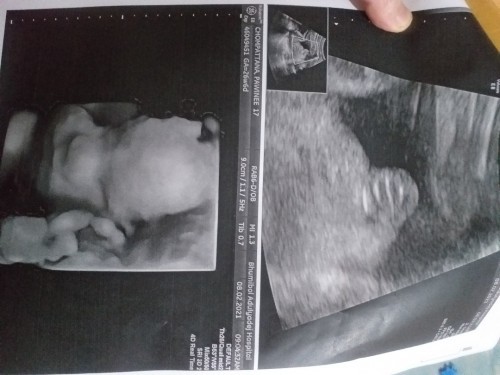

แม่ๆช่วยดูหน่ยค่ะหญิงหรือชาย

หมอบอกว่าหนูเป็นหญิงแต่ทำไมเหมือนหนูมีจู๋เลย

ดูไม่ออกเลยค่ะว่าหมอซูมส่วนไหนมา แต่ดูจากรูปใหญ่ที่หมอซูมน่าจะเหมือนนิ้วมือเลย

ไม่มีรูปหว่างขาน้องค่ะ บอกไม่ได้ค่ะ

ญ จ้า ถ้าชายจู๋จะโด่ออกมาเลย

ญ ค่ะแม่มาเป็นกลีบเลยค่ะ

ญ ค่ะ 3ขีด